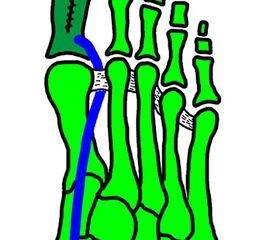

Klinisches Erscheinungsbild eines Hallux varus (eigenes Bildmaterial)

Abbildung 1